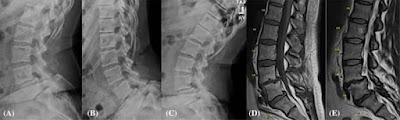

Los investigadores recogieron muestras de disco de cirugías y estudios de imagen, junto con muestras de sangre, heces y saliva de pacientes con y sin espondilolistesis degenerativa lumbar. Esta afección, que suele ser común, implica el deslizamiento de un cuerpo vertebral sobre otro debido a la degeneración del disco intervertebral o de la articulación facetaria, y puede provocar dolor y discapacidad.